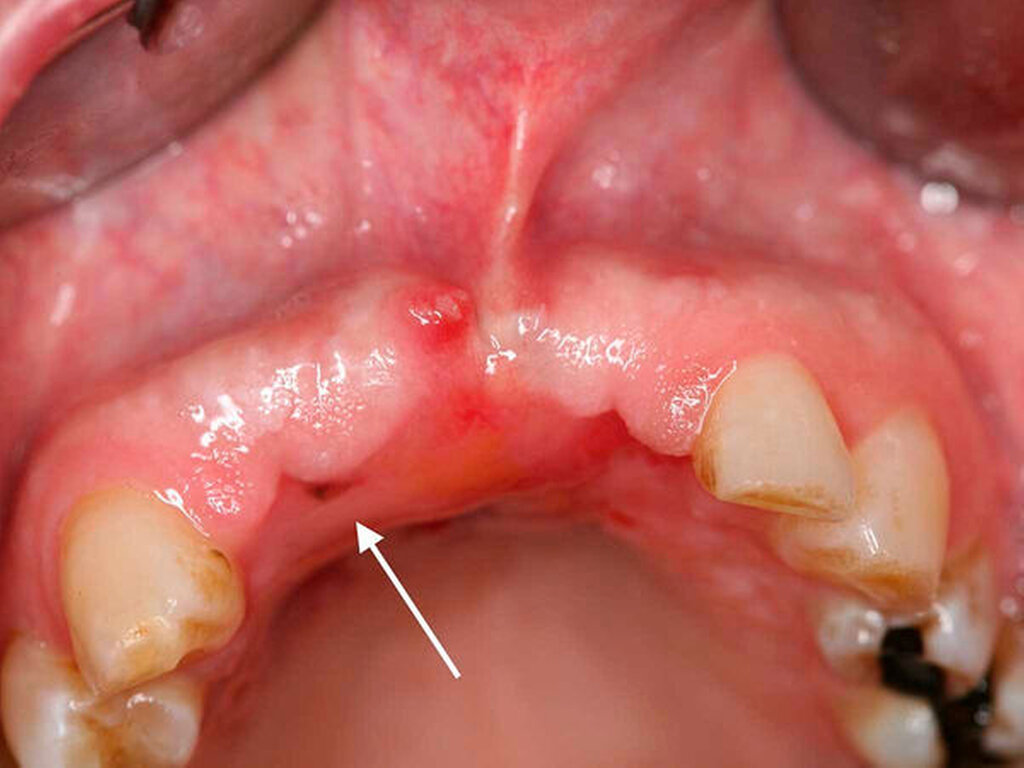

Nach drei Monaten war erneut eine circa 2 mm x 2 mm große schwärzliche Mundschleimhautveränderung in regio 012 auffällig (Abbildung 4). Die Raumforderung inklusive einer kortikalen Knochenspange des Alveolarkamms und des Os palatinum von regio 13 bis regio 23 wurde großflächig reseziert. Histopathologisch wurde ein R0-reseziertes Rezidiv des vorbekannten Melanoma in situ bestätigt, eine tiefere Tumorinfiltration über die Basalmembran hinweg oder sogar bis in den ortsständigen Knochen konnte ausgeschlossen werden.